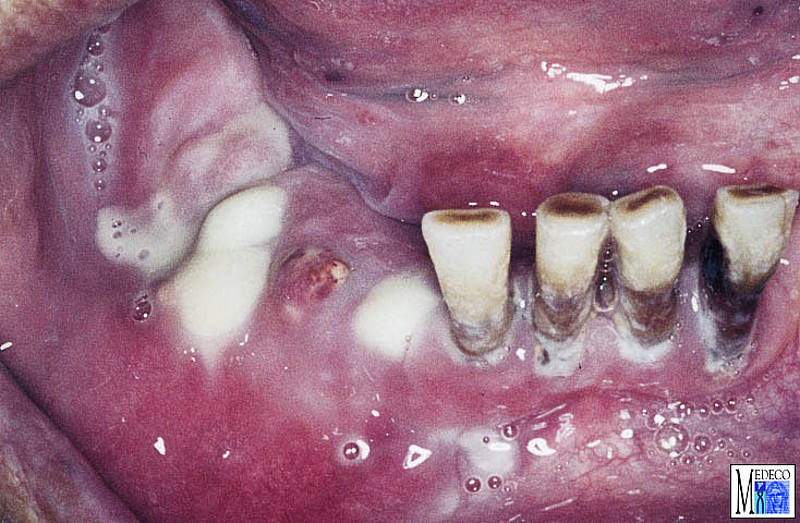

Entzündungen der Kieferknochen from www.medeco.de

Entzündungen der Kieferknochen

Osteosarkom des Unterkiefers. Nach einer Zahnextraktion ist es nicht ungewöhnlich, dass bei bis zu 30% der Patienten tatsächlich Knochensplitter oder der Knochen selbst aus dem Zahnfleisch ragen Kieferknochen bricht durchs Zahnfleisch!? 25.86K aufrufe 10